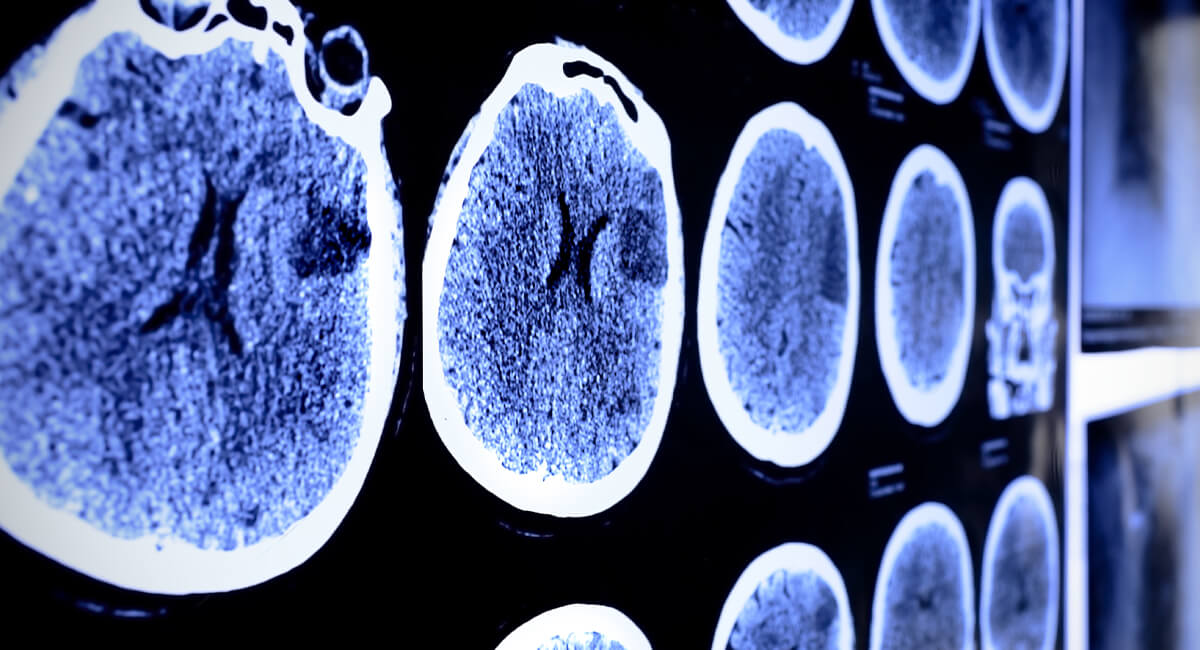

These early successes laid the foundation for a broader class of implantable systems that interact with the nervous system. Devices targeting the brain and peripheral nerves emerged to treat epilepsy, Parkinson’s disease and chronic pain. Over time, these systems evolved from simple stimulators into platforms capable of sensing, processing and responding to biological signals.

In the past decade, closed-loop neural devices and brain-computer interfaces (BCIs) have entered clinical use. For many patients, the impact has been transformative: reducing tremor, restoring movement, and enabling communication for individuals with severe paralysis through direct neural control of external devices.

Neural interfaces represent a fundamental shift in how humans may interact with machines. Rather than relying on external gestures or speech, these systems connect directly with neural activity, enabling bidirectional communication between biological and digital systems. In clinical settings, this enables treatment through sensing and modulation of the body’s own control signals. More broadly, it aligns machines more closely with intent, state and adaptation.